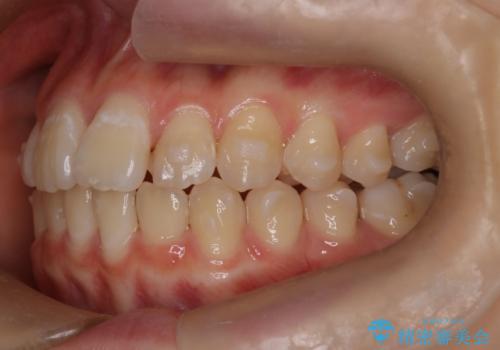

- 前歯のガタツキが気になるとのことで来院されました。

前歯のガタツキに加え、奥歯の噛み合わせにも問題があったため、マウスピース矯正で治療し改善しました。